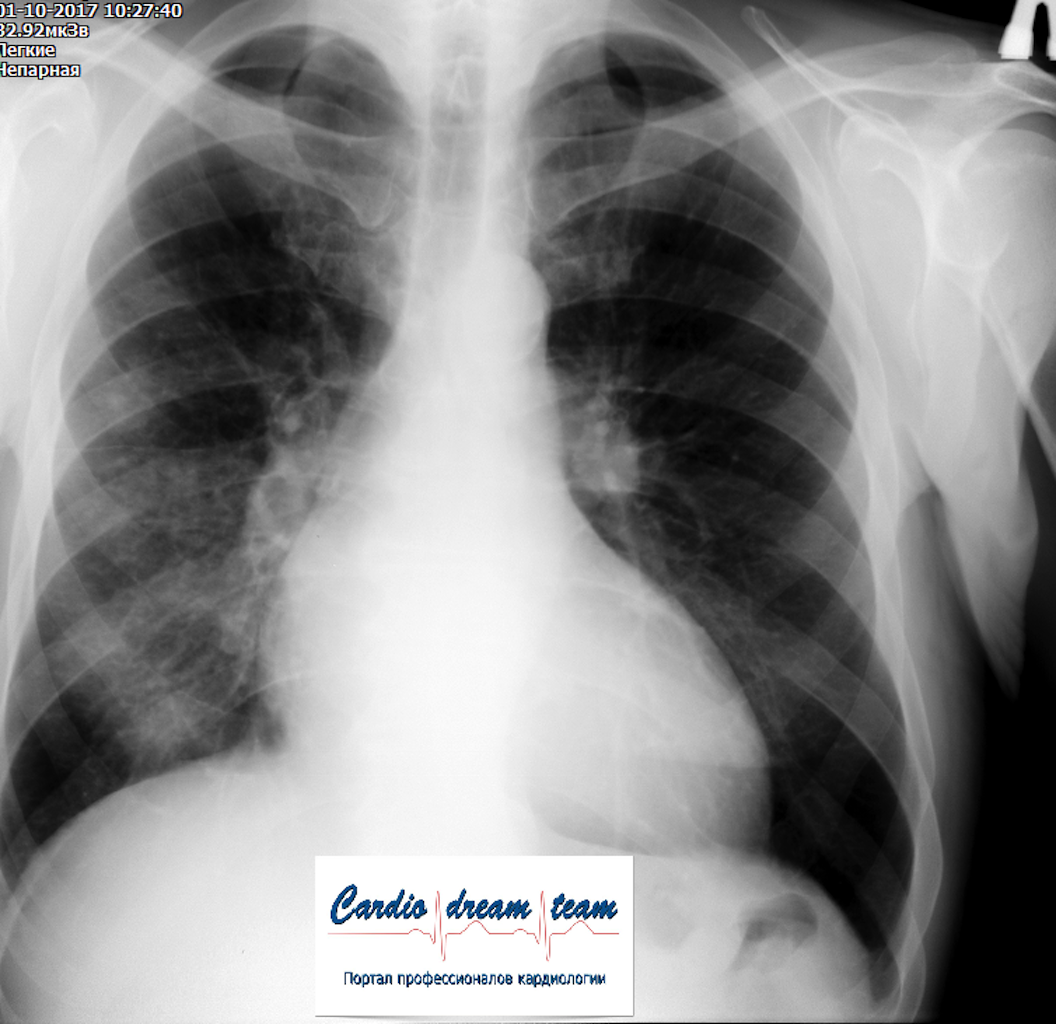

Двухсторонняя полисегментарная

Вложения:

IMG_5197 2.png

IMG_5197 2.png [ 773.14 KiB | Просмотров: 23853 ]